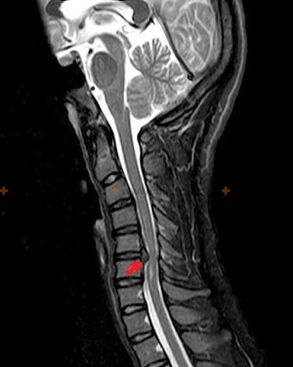

Η οστεοχόνδρωση είναι μια διάγνωση ακτίνων Χ, καθώς μια λεπτομερής κλινική εικόνα είναι διαθέσιμη μόνο τη στιγμή της έξαρσης, ενώ αλλαγές στη σπονδυλική στήλη μπορούν να συμβούν με πλήρη υποκειμενική ευημερία ενός ατόμου. Χωρίς εξέταση με ακτίνες Χ, μπορούμε να μιλήσουμε μόνο για υποψία οστεοχόνδρωσης, επειδή παρόμοια συμπτώματα μπορεί να προκληθούν από άλλες ασθένειες (μυοσίτιδα, σπονδυλικά νεοπλάσματα και άλλα).

Για τη διάγνωση της οστεοχόνδρωσης χρησιμοποιούνται οι ακόλουθες ερευνητικές μέθοδοι: ακτινογραφία (κατά προτίμηση με λειτουργικές εξετάσεις), MSCT και MRI. Η τελευταία μελέτη είναι περισσότερο προτιμότερη λόγω του γεγονότος ότι επιτρέπει σε κάποιον να απεικονίσει πολύ καθαρά την κατάσταση των μεσοσπονδύλιων δομών.

Τα σημάδια της οστεοχόνδρωσης με ακτίνες Χ περιλαμβάνουν τις ακόλουθες αλλαγές στη σπονδυλική στήλη:

- Μειωμένο ύψος μεσοσπονδύλιων δίσκων.

- Παρουσία οριακών οστικών αναπτύξεων.

- Παραβίαση της θέσης των σπονδύλων σε σχέση μεταξύ τους.

- Παραμορφώσεις σπονδυλικών σωμάτων και τόξων κ.λπ.

Η παρουσία των αλλαγών που περιγράφονται παραπάνω, καθώς και οι αλλαγές στη δομή του μεσοσπονδύλιου δίσκου, που ανιχνεύονται με MSCT και MRI, χρησιμεύουν ως αξιόπιστα σημάδια που επιβεβαιώνουν την παρουσία οστεοχονδρωσίας.